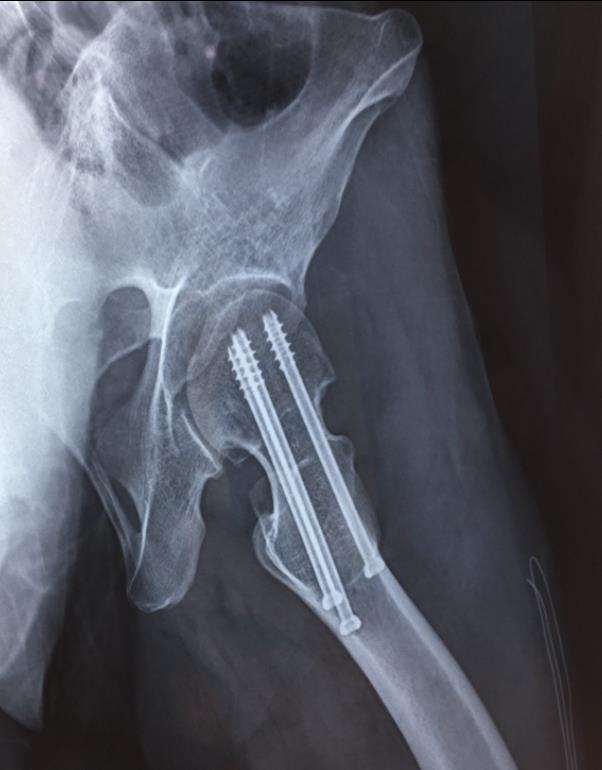

2、复位标准:C-B透视

正位:Shenton's线恢复;恢复股骨颈135°以上的颈干角,大粗隆尖端与股头中心在同一平面;骨折断端阳性支撑。

侧位:股干、颈、头的中心排成一条直线。

越近于解剖对位,骨折不愈合及股骨头缺血性坏死发生率越低。

2、标准放置螺钉为倒三角形,其中下方螺钉在股骨矩,后方螺钉在后方骨皮质、研究发现倒三角形平行三枚螺钉能提供最佳的固定强度;

3、螺钉位于股骨颈四周,特别是后侧及下方,避免低于小转子方向进针,可能导致术后转子下骨折;

4、两个平面透视导针位置良好后切开皮肤,空心钻铭孔,导针引导下拧入空心钉,空心钉确保所有螺纹位于骨折线近端,螺钉头应距离软骨下骨5mm。

空心钉固定的三原则:“贴边、平行、倒品”。

1、贴边是指3枚螺钉在股骨颈内,尽量靠近外围皮质。这样3枚螺钉作为一个整体,对整个骨折面可形成面状加压,如果3枚螺钉不够离散,更趋于点状加压,稳定性较差,不能较好地对抗扭转和剪切。

3、平行生物力学更稳定。